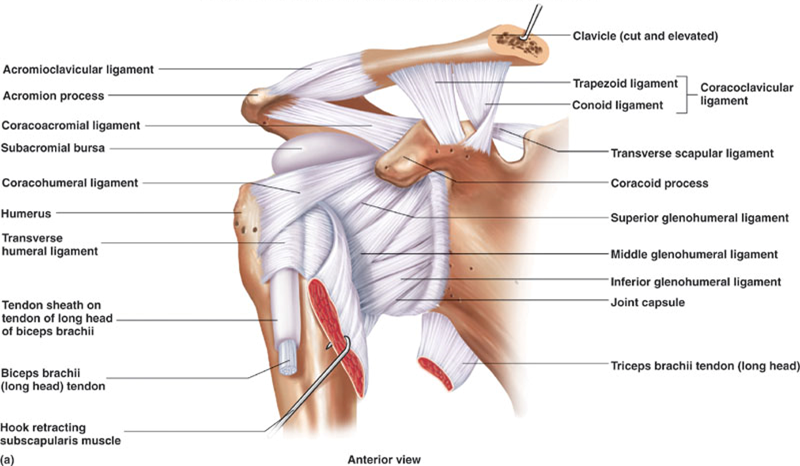

Glenohumeral ligament: анатомия и функции плечевого сустава